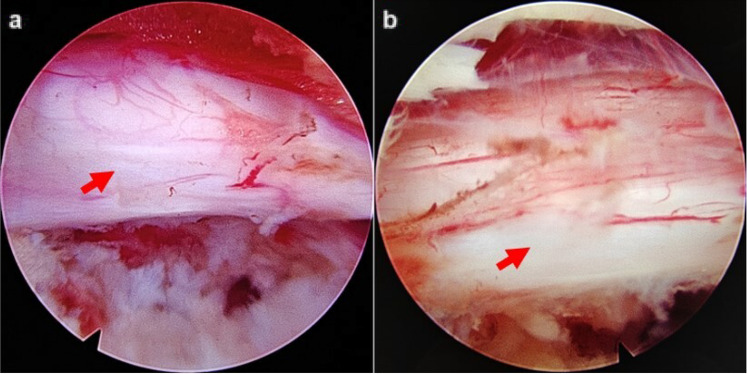

Methods: From January 2019 to December 2020, 60 patients who had LDH with grade I degenerative spondylolisthesis were divided into two groups. Group A adopted TELD while Group B adopted CN combined with CCNL. The surgical efficacy was evaluated according to the visual analogue scale (VAS), oswestry disability index (ODI), quality of recovery-15 (QoR-15), and modified MacNab criteria. Imaging findings including lumbar lordosis (LL), segmental lordosis angle (SL), slip percentage (SP), and disc height (DH) were compared between the two groups pre-operation and at the last follow-up.